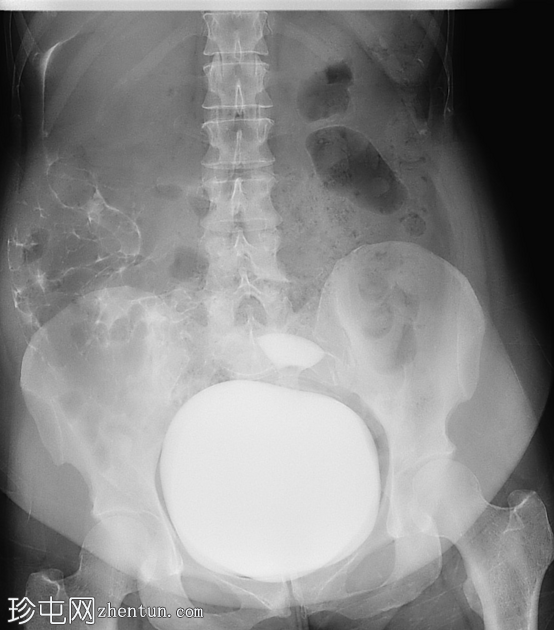

正位

经Foley导尿管向膀胱内注入约700毫升造影剂。

子宫内可见造影剂积聚,膀胱上表面与子宫之间存在异常瘘管连接。同时可见造影剂从输卵管溢入腹腔。

影像

学表现符合膀胱子宫瘘。